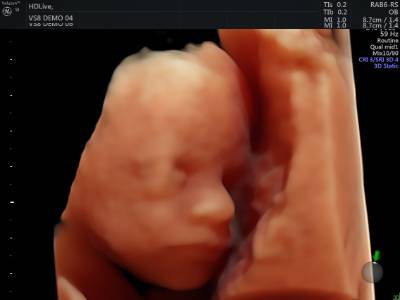

Hoy en día, la ecografía 3D y 4D permiten ver la morfología del feto y su reconstrucción en tres dimensiones. Con la aplicación en 4D es posible además contemplar al feto en movimiento, interpretando también su relación con el medio.

Desde el punto de vista afectivo, la obtención de imágenes de gran calidad y realismo, que suelen ser más fáciles de interpretar para los padres, proporciona indudables ventajas de tipo psicológico, mejora la relación de la madre con el feto y la gestión de los síntomas provocados por el embarazo.

Sin embargo, advierte la Dra. Moreno, "no olvidemos la necesidad de que esta prueba sea realizada por especialistas en obstetricia y ecografía fetal, ya que las imágenes pueden conducir a graves problemas de interpretación."